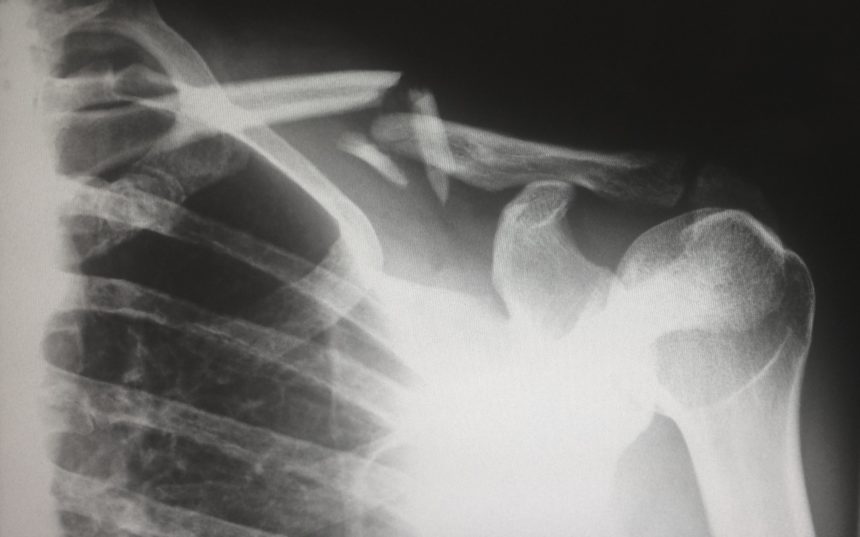

Jeszcze jedną, popularną grupą przypadków złamania kości, są złamania kości długich, które najczęściej występują w okresie jesienno- zimowym, a związane jest to ze zwiększoną liczbą upadków.